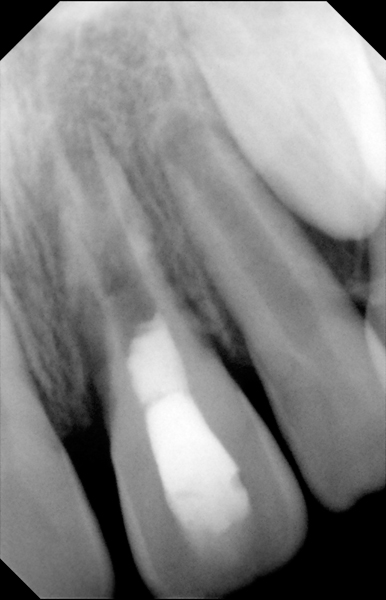

Clinical procedure: If apical bone loss is present (Figure 1) a collagen/gelatin sponge (eg, Gelfoam®, Pfizer Inc., www.pfizer.com) can be placed apically so that the MTA can be delivered to the desired working length. (Any other surgical resorbable sponge would also work, such as OraPlug® [Salvin Dental Specialties, www.salvin.com], Surgifoam® [Midwest Dental, www.mwdental.com], or Surgispon® [Aegis Lifesciences, www.surgispon.com]). This is done by taking a small piece (2 mm x 2 mm) of the resorbable sponge and pushing it down to and through the root apex with an endodontic file. Once this is done, MTA is packed down the canal with a custom-fitted cone. The clinician can use a rubber stopper on the gutta-percha cone to know the exact length of MTA placed in the apical third (Figure 2). Once the apical third is sealed with 3 mm to 5 mm of MTA, the remaining coronal canal space can be back-filled using a warm gutta-percha technique (Figure 3).

Fig 2. MTA placed in the apical third.

Figure 2